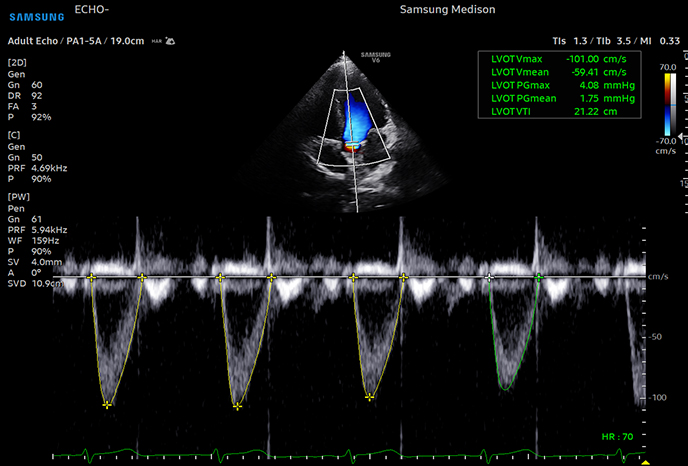

고급 도플러 기능으로 심혈관 평가 및 이상 감지

심장심장의 해부학 구조 및 혈류역학적 평가, 순환기계 장애, 심장 수축·이완

하트어시스트

자동 EF(박출률) 계산